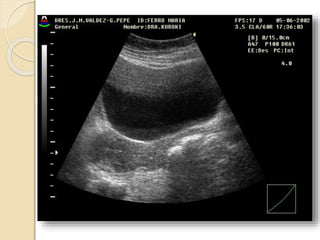

FIBROMA O LEIOMIOMA UTERINO

Patología común del útero que ocurre aproximadamente

en el 40% de las mujeres mayores de 35 años.

Los fibromas habitualmente son múltiples y más

comúnmente asintomáticos.

Se clasifican en:

• Submucosos: son los menos frecuentes pero es mas

probable que produzcan síntomas.

• Intramurales: Es el tipo mas común.

• Subserosos: Con frecuencia son pediculados y

pueden simular masas anexiales.

Patología Uterina FIBROMAO LEIOMIOMA UTERINO Patología común del útero que ocurre aproximadamente en el 40% de las mujeres mayores de 35 años. Los fibromas habitualmente son múltiples y más comúnmente asintomáticos. Se clasifican en: • Submucosos: son los menos frecuentes pero es mas probable que produzcan síntomas. • Intramurales: Es el tipo mas común. • Subserosos: Con frecuencia son pediculados y pueden simular masas anexiales.